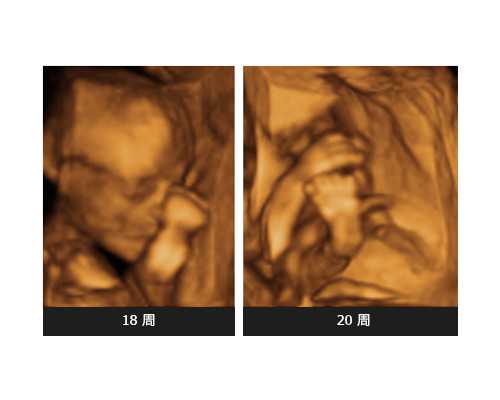

2. 促排卵和取卵

需要在医生的指导下使用促排卵药物,刺激卵巢产生多个卵泡。当卵泡成熟后,医生会通过取卵手术取出卵子。